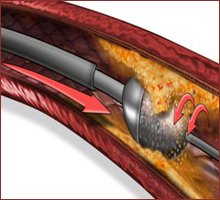

Rotablation uses a tiny drill with a #diamond-tipped burr, powered by compressed air to break up calcified plaque (hard block) that is clogging the coronary artery.

The other approach is a rotablator which is basically a diamond coated drill with which you can drill into the calcium and clear blockages. But it cannot be used in acute heart attacks. More for chronic blockages. #Rotablation #MedTwitter #cardiotwitter

Severely calcified coronary arteries require advanced precision. Rotablation modifies rigid plaque using a diamond-tipped device, enabling optimal stent expansion and restoring smooth blood flow in complex coronary artery disease. #Rotablation #InterventionalCardiology